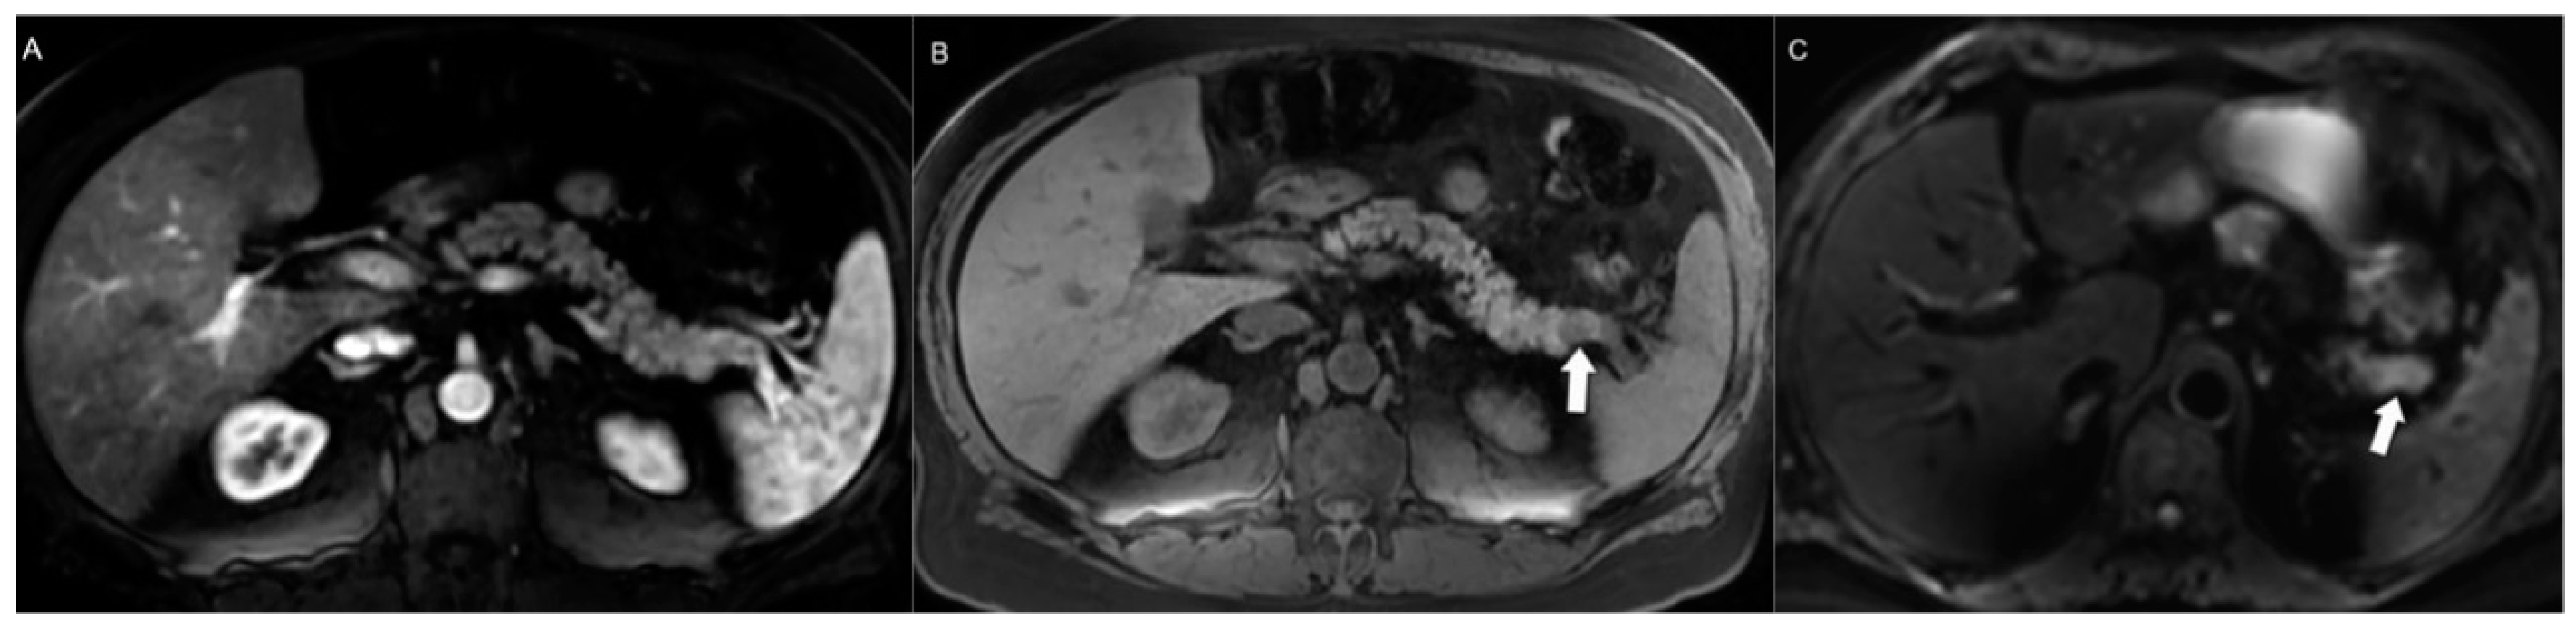

- d’Assignies, G.; Fina, P.; Bruno, O.; Vullierme, M.-P.; Tubach, F.; Paradis, V.; Sauvanet, A.; Ruszniewski, P.; Vilgrain, V. High Sensitivity of Diffusion-Weighted MR Imaging for the Detection of Liver Metastases from Neuroendocrine Tumors: Comparison with T2-Weighted and Dynamic Gadolinium-enhanced MR Imaging. Radiology 2013, 268, 390–399. [Google Scholar] [CrossRef]

- Hwang, E.J.; Lee, J.M.; Yoon, J.H.; Kim, J.H.; Han, J.K.; Choi, B.I.; Lee, K.-B.; Jang, J.-Y.; Kim, S.-W.; Nickel, M.D.; et al. Intravoxel Incoherent Motion Diffusion-Weighted Imaging of Pancreatic Neuroendocrine Tumors. Investig. Radiol. 2014, 49, 396–402. [Google Scholar] [CrossRef] [PubMed]

- Mebis, W.; Snoeckx, A.; Corthouts, B.; El Addouli, H.; Nicolay, S.; Van Hoyweghen, A.; Spinhoven, M.; de Beeck, B.O. Correlation Between Apparent Diffusion Coefficient Value on MRI and Histopathologic WHO Grades of Neuroendocrine Tumors. J. Belg. Soc. Radiol. 2020, 104, 7. [Google Scholar] [CrossRef] [PubMed]

- Zong, R.L.; Geng, L.; Wang, X.; Xie, D. Diagnostic Performance of Apparent Diffusion Coefficient for Prediction of Grading of Pancreatic Neuroendocrine Tumors. Pancreas 2019, 48, 151–160. [Google Scholar] [CrossRef] [PubMed]